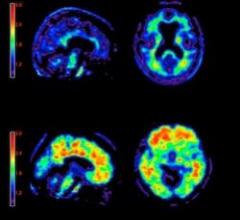

June 1, 2020 — TAUVID, a radioactive diagnostic agent, has been approved by the FDA for positron emission tomography ...

Eli Lilly and Co. and Avid Radiopharmaceuticals Inc. announced a Phase 3 study of positron emission tomography (PET) imaging agent flortaucipir F-18 met its two primary endpoints, defined as predicting brain tau pathology and predicting Alzheimer's disease diagnosis.

The U.S. Food and Drug Administration (FDA) has approved the first diagnostic agent to image Alzheimer’s disease beta-amyloid neuritic plaques in the living brain. Previously, the only way to confirm diagnosis of these plaques was from post-mortem biopsies. Eli Lilly and Company and Avid said the FDA cleared the commercial release of florbetapir (Amyvid).